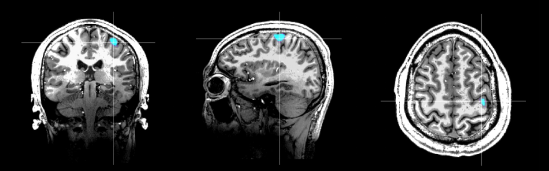

图:Marvel MEG®脑磁图仪健康人右手运动功能区与7.0T核磁影像融合结果

Marvel MEG®无液氦脑磁图仪是基于完全自主知识产权的新型生物极弱磁场探测技术——原子磁力计研发而成,对脑部磁场的探测灵敏度达到了10fT– 15fT(1fT = 10-15Tesla,地球磁场的十亿分之一)。Marvel MEG®无液氦脑磁图仪以非侵入方式检测和显示大脑神经组织放电活动产生的磁场信号,进行脑功能成像和精准定位。该产品兼备毫秒级的时间分辨率和毫米级的空间分辨率,同时无创、无辐射、无需造影剂,并集成高精度磁场控制系统和多模态刺激系统,可为神经系统疾病的科学研究和临床应用提供无创、精准诊断的手段。这一国产高科技装备早前已获批北京市创新医疗器械,并在北京天坛医院进行注册临床研究。通过对比研究发现,Marvel MEG®无液氦脑磁图仪使常温下实现超高灵敏度的磁场探测成为可能,可解决传统超导SQUID脑磁图的痛点,具备常温工作、无需液氦,无需建设单独的磁屏蔽房,检测效率高等独特优势,大大提升了创新产品的可及性。